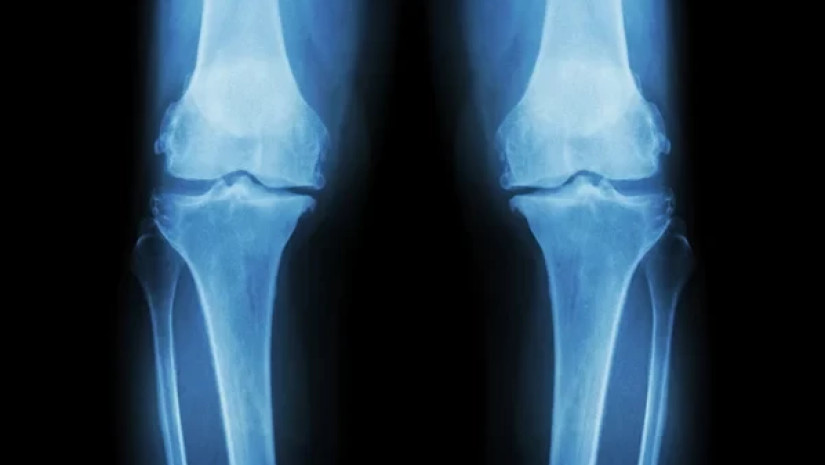

ამან მეცნიერები აიძულა განეხილათ, შესაძლოა თუ არა 15-PGDH ჩართული იყოს ოსტეოართრიტში — დაავადებაში, რომელშიც სახსრებზე დატვირთვა განაპირობებს ხრტილში კოლაგენის დაშლას, რაც ანთებას და ტკივილს იწვევს.

ხანდაზმულ თაგვებზე ჩატარებულ ცდებში, 15-PGDH ინჰიბიტორის (მბლოკავი) შეყვანის შემდეგ, მუხლის გაცვეთილი ხრტილი კვლავ გასქელდა. ახალგაზრდა თაგვებზე ჩატარებულ ასეთივე ცდებში, ინჰიბიტორმა ისინი დაიცვა ტრავმით გამოწვეული ოსტეოართრიტის ჩვეულებრივი ეფექტებისგან.

როდესაც მკვლევრებმა თაგვებში ხელოვნურად გამოიწვიეს წინა ჯვარედინი იოგის დაზიანების ეკვივალენტი და შემდეგ უმკურნალეს, ოსტეოართრიტი აღარ განვითარდა, რაც როგორც წესი, მოსალოდნელია ხოლმე ამ სახის სამოდელო თაგვებში.

დამუშავებულ თაგვებს უფრო სტაბილური სიარული ჰქონდათ, რაც მიუთითებს, რომ განიცდიდნენ ნაკლებ ტკივილს; ასევე, დაზიანებულ ფეხებზე იტანდნენ უფრო მეტ წონას — ნიშანი იმისა, რომ ხრტილის აღდგენა ფიზიკური ჯანმრთელობის გაუმჯობესებას უტოლდებოდა.

ასეთივე ექსპერიმენტი სცადეს იმ ადამიანებისგან აღებული ქსოვილების ნიმუშებზე, რომლებსაც მუხლის ჩანაცვლების ოპერაცია ჰქონდათ ჩატარებული. აქაც დაფიქსირდა აღდგენის მკაფიო ნიშნები, ხრტილი გახდა უფრო მაგარი და აღენიშნებოდა ანთების მხოლოდ მცირე ნიშნები.